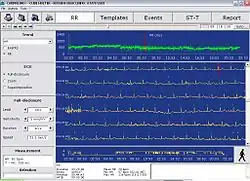

Older monitors used reel-to-reel tapes or C90 or C120 audio cassettes, moving at a 1.7 mm/s or 2 mm/s speed to record the data. The recording could be played back and analyzed at 60 times the recording speed, so 24 hours of recording could be analyzed in 24 minutes. Modern monitors record EDF-files on digital flash memory. The information is loaded on a computer, which counts ECG complexes; calculates summary statistics, such as average, minimum, and maximum heart rate; and finds parts of the recording that are worthy of further study.

Analyzing software

After the recording of ECG signal for typically 24 hours, the signal must be analysed. A person would have to listen for the full 24 hours; instead integrated automatic analysis determines different sorts of heart beats, rhythms, etc. The success of the analysis is closely associated with the signal quality, which mainly depends upon the attachment of the electrodes to the patient's body. Incorrect attachment allows electromagnetic disturbance to add noise to the record, particularly with rapid patient movement, impeding processing. Other factors can also affect signal quality, such as muscle tremors, sampling rate and resolution of the digitized signal (high quality devices offer higher sampling frequency).

The automatic analysis commonly provides the physician with information about heart beat morphology, beat interval measurement, heart rate variability, rhythm overview and patient diary (moments when the patient pressed the patient button). Advanced systems also perform spectral analysis, ischemic burden evaluation, graph of patient's activity or PQ segment analysis. Also possible is the ability to monitor and analyse pacemaker impulse detection, useful for checking pacemaker function.